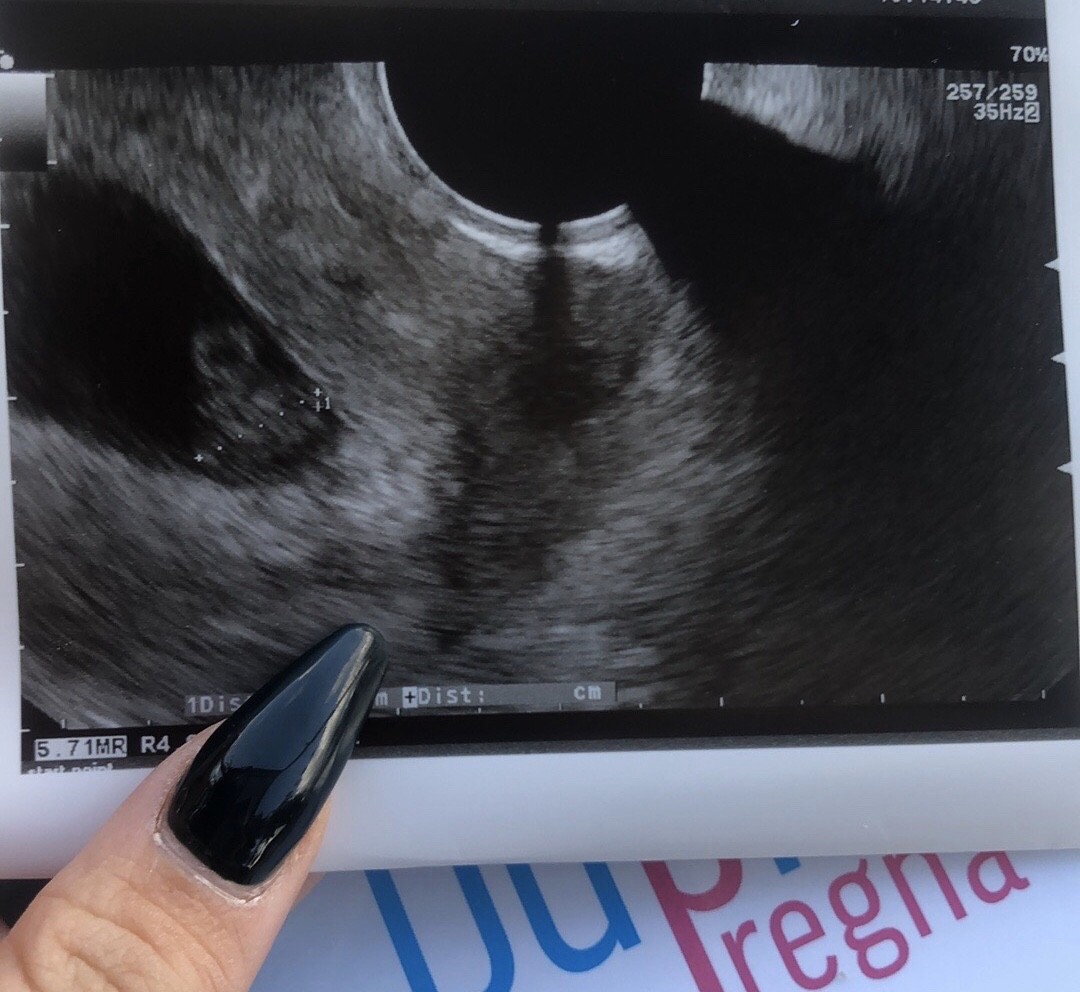

Widziałam bijące serduszko [emoji173]️